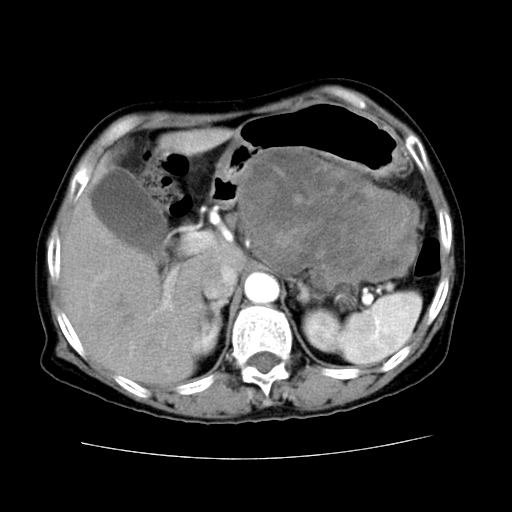

女性,72岁。

主诉中上腹部疼痛不适1年余。

胰腺尾部不规则巨大略低密度肿块,界限清楚,内密度不均,增强动脉期不均匀强化,门脉期明显退减并低于胰腺密度,肿瘤包埋于脾血管。多考虑;来源于胰腺尾部的“胰腺癌”。

1、这个病例确实有点难。影像主要显示胰腺体尾部占位,我们当初也是诊断胰体尾部囊腺癌可能性大,而且读片会上也很多人这么诊断的。

2、手术所见:打开腹腔发现胃与胰腺体尾部可见肿块,大小约10×8×11cm,质硬,不可推动,周围血供丰富。术中诊断:胃肿瘤侵及胰腺体尾部。

1)、胃小弯侧胃肠间质瘤(考虑恶性),瘤体大小13.5×7×6.5cm,上下切缘阴性。

2)、胃小弯1只、幽门下2只淋巴结慢性炎。免疫组化:cd117(+)、cd34(+)、sma(+)、desmin(-)、s-100(-)、ki-67<10%(+).

4、这个肿瘤太大了,而且密度不均性强化,从这点我们应该不能单纯诊断胰腺癌,而应想到目前流行的胃肠道间质瘤。这个肿瘤主要发生于胃壁浆膜层,所以显示与胃壁关系不是很紧密,故而大多认为是胰腺癌。